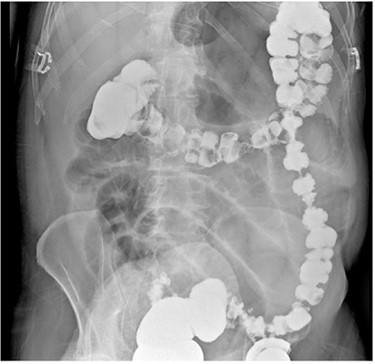

A 67-year-old male with a past medical history of prostate cancer, hypertension and prior open right inguinal hernia repair presented to the emergency department (ED) with sudden onset nausea, vomiting and abdominal pain for 2 h. The abdomen was non-distended and slightly tender in the epigastrium. A clinical diagnosis of pancreatitis was made based on physical examination, history and a mildly elevated lipase and the patient was discharged home with antiemetic medications by the ED providers. The patient presented back to the ED 2 days later with worsening abdominal pain, nausea, vomiting and obstipation. At this time his abdomen was distended and tender to palpation in the epigastrium without peritoneal irritation. Due to his obstructive clinical picture, a CT scan of the abdomen and pelvis with IV contrast (Fig. 1) was obtained in the ED. The scan was read as a possible volvulus versus an internal hernia causing small bowel obstruction. A nasogastric tube was placed after he was admitted to the surgical unit with partial resolution of his abdominal tenderness and distention. A barium enema (Fig. 2) was performed to rule out an obstructing distal mass, which showed a transition point at the hepatic flexure.

CT scan of the abdomen and pelvis with IV contrast. (A) Coronal view shows internal herniation of the cecum through the foramen of Winslow. (B) Axial view demonstrates the same findings with the stomach displaced both laterally and anteriorly by the cecum. Of note there was 1.5-cm ring-enhancing lesion located in the body of the pancreas found incidentally.